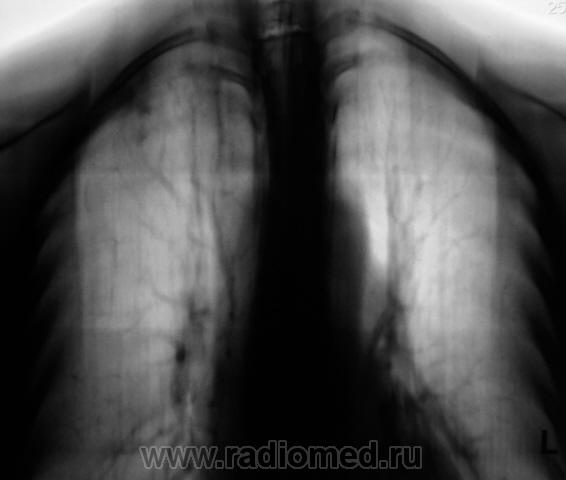

Пол пациента: Мужской пол Тип патологии: Инфекция Область исследования: Грудная клетка и верхние дыхательные пути Методы исследования: Rg После прохождения флюорографии взяли пациента на контроль, дообследовали и направили к коллегам-фтизиатрам. Пациент жалоб не предъявляет. Ваше мнение коллеги? Чт, 24/12/2009 - 14:18 #1 serega Не на сайте Был на сайте: 12 лет 4 месяцев назад Зарегистрирован: 15.10.2009 - 18:10 Публикации: 99 Здравствуйте, Валентин Львович. Тут по моему tbs. А почему Вы "боковушки" не наврезали? Или Вы посчитали, что и так всё ясно? Чт, 24/12/2009 - 14:26 #2 Катенёв Валенти... Не на сайте Был на сайте: 7 лет 3 недели назад Зарегистрирован: 22.03.2008 - 22:15 Публикации: 54876 Здравствуйте уважаемый serega ! Клиника типична - "клиники никакой", жалоб нет. Скиалогия также типичная, сомнений по поводу "очагового" не было. Выполнили "фтизиатрический стандарт" и отдали фтизиатрам.

Клиника типична - "клиники никакой", жалоб нет. Скиалогия также типичная, сомнений по поводу "очагового" не было. Выполнили "фтизиатрический стандарт" и отдали фтизиатрам.